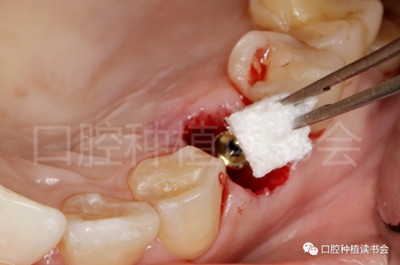

5.3.4 旋入覆蓋螺絲,在種植體與四周骨壁的間隙內(nèi)植入 Bio-Oss Collagen,植骨材料用生理鹽水濕潤(rùn)后,用15#刀片分割為小塊分別植入,并用充填器壓實(shí)(圖17)。

圖17 后牙即刻種植植骨推薦使用骨膠原材料,有利于軟組織愈合。